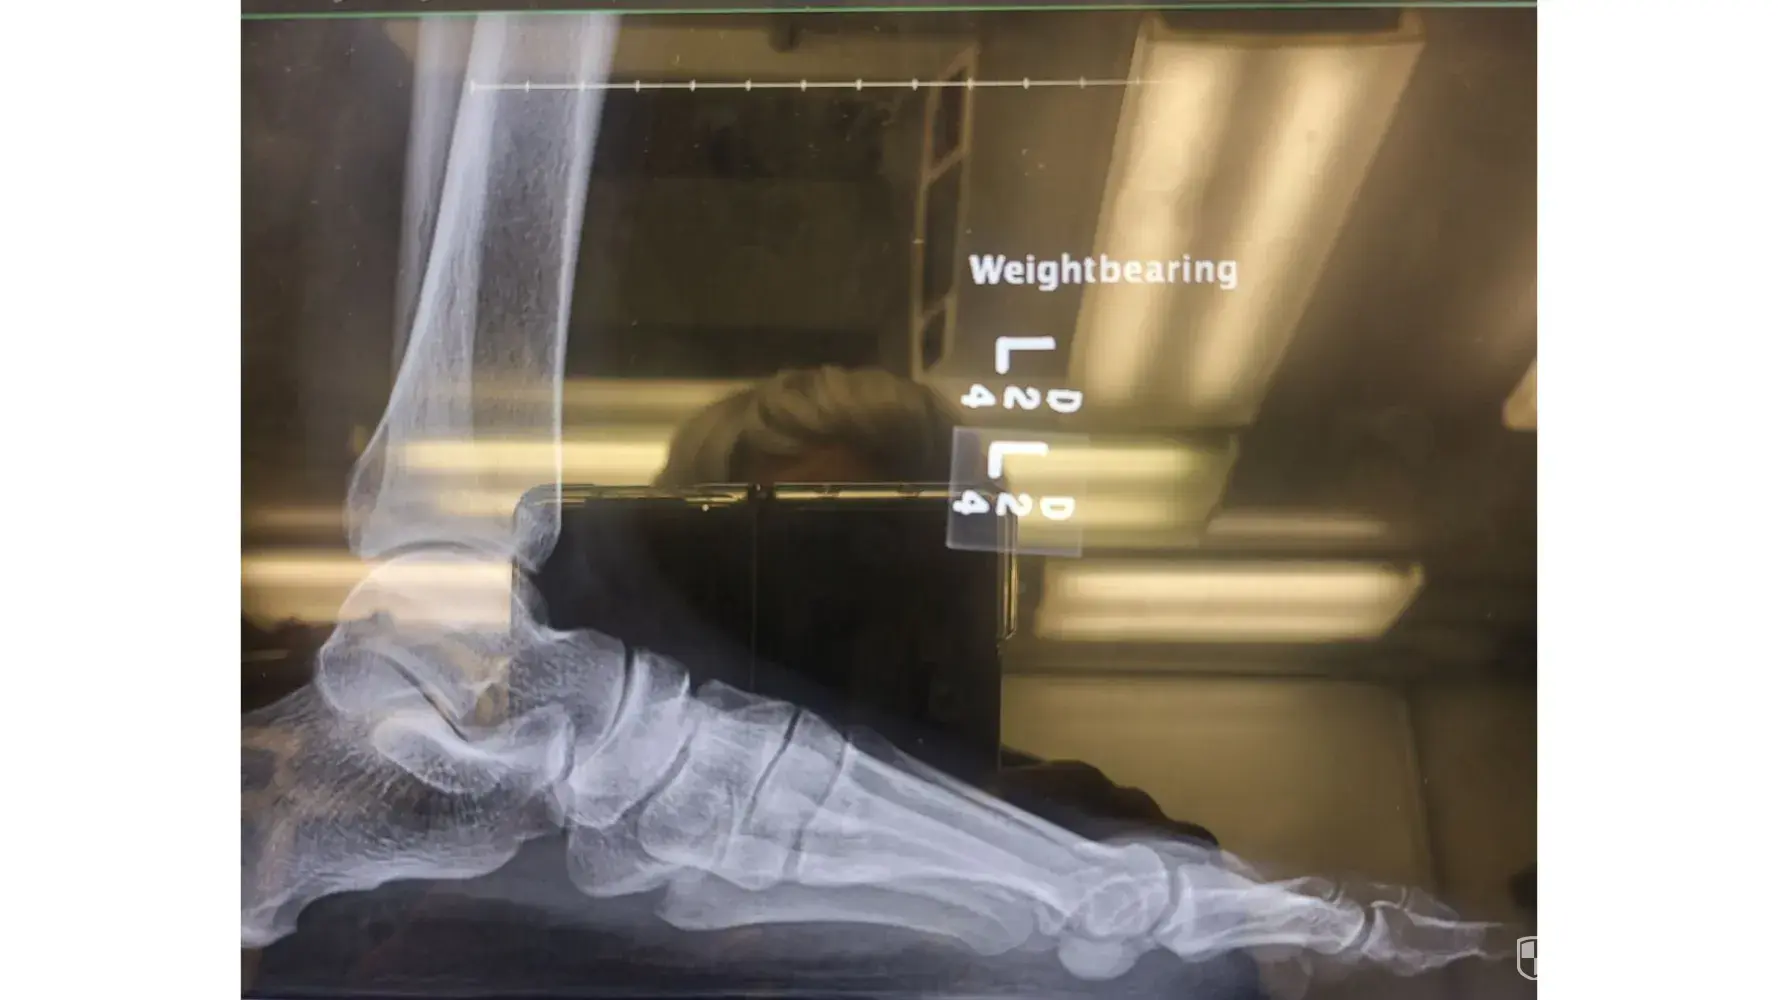

I checked in the resort on December 1, 2022. I prepaid for a Marvelous suite Months ago to celebrate my Birthday in Panama City. When I entered the room #1923. I went to sleep after a long day of travel. As the daylight began to come through the patio door I got up to close the curtains. Without realizing the sofa bed (let out murphy bed) between the King bed and patio door was broken and protruding out at the bottom. This area should've been flush to the sofa. My foot hit the edge of this and caused severe pain. I laid back down until morning break. I called down to the hotel lobby from the room to report what happened. I was instructed someone would be coming up to take a look. No one ever showed up. Later in the day (Dec. 2nd) after elevating my leg in the room I came down to speak with someone at the desk. A report was made in the resort computer By Domingo. I also spoke with David about the matter. Maintenance was asked to go to the room to fix the sofa and ice was sent up. It was a failed attempt, the piece still protruded away from the sofa. I asked for a Manager, I was told he would not be in until the next morning. In the meantime An EMT from the resort was asked to come look at the foot. She did a quick look and concluded it was NOT fractured but bruised. Her Recommendation was to ice and elevate the foot and to stay off of it. She said it will hurt and stay swollen for a few days. This was not my idea for a vacation. The next morning (Dec. 3rd) I stopped at the desk limping. My entire foot was swollen and throbbing. I spoke to David again and showed him my swollen foot from the injury. I waited for the Manager to become available. He spoke with me and apologized for the inconvenience. He offered to move me to another room which I did to avoid any further injuries. On Dec 4th I checked out. I When I arrived home I still had pain and trouble walking but expected to get better according to the Resorts EMT. On December 14th, 2022 I went to the Friends Family Health Clinic because there was no relief. The Nurse indicated that the swelling would have gone down before now if it was only bruised and ordered an Xray. I went directly to the University Of Chicago Hospital for the Xray. I received a call shortly after arriving back home from the Doctor, he confirmed that the left foot 2nd toe is fractured. (broken). This has caused me PAIN & SUFFERING. It has been difficult to function daily duties at home or work.

Desired outcome: Refund for entire stay at the RIU and reimbursement for prepaid activities that I could not enjoy. Doctor visits. Pain & Suffering. Total $5,000.00Monica J Allen708-945-9925

Update by Monica J Allen

Dec 15, 2022 12:19 pm UTC

photos from Xray